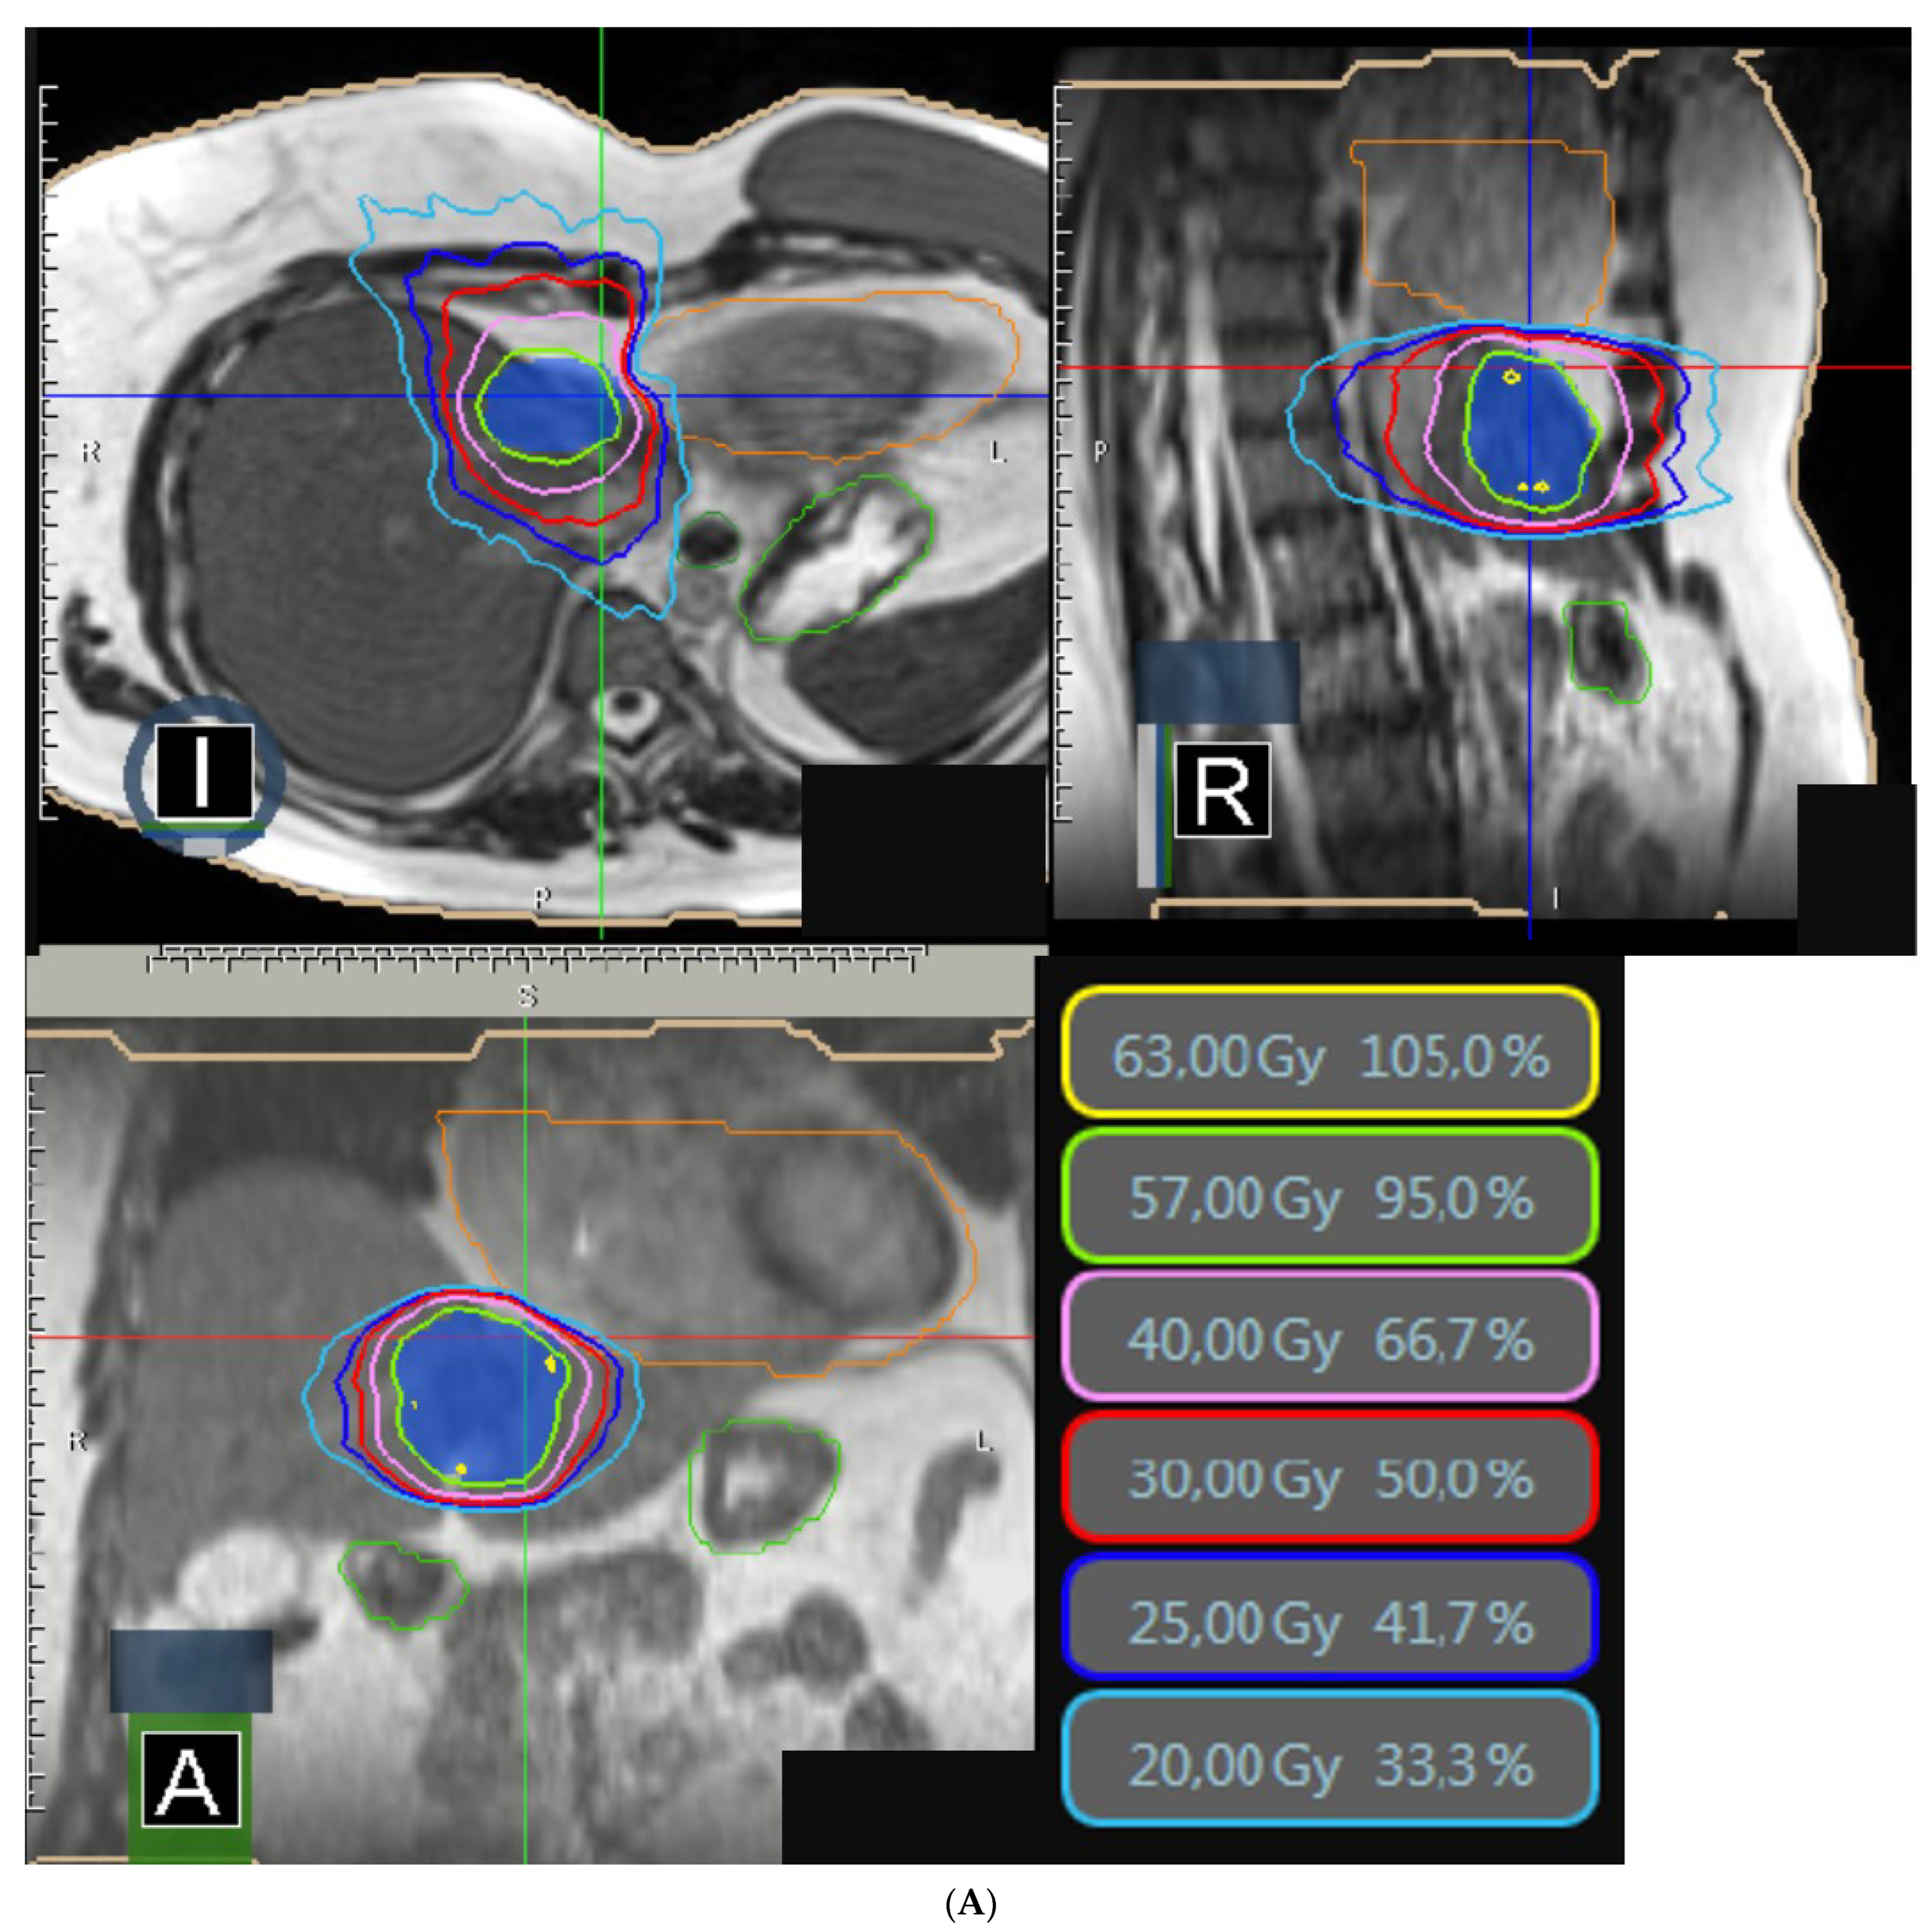

| Total Dose (Gy) | |

| 60 50 40 35 30 | 2 (6.5%) 3 (9.7%) 1 (3.2%) 17 (54.8%) 8 (25.8%) |

| PTV | |

| V95% (%) V100% (%) D95% (Gy) D1cc (Gy) | 95.9 (71.6–98.9) 50.0 (49.2–90.8) 47.5 (26.9–58.0) 52.0 (41.2–63.1)) |